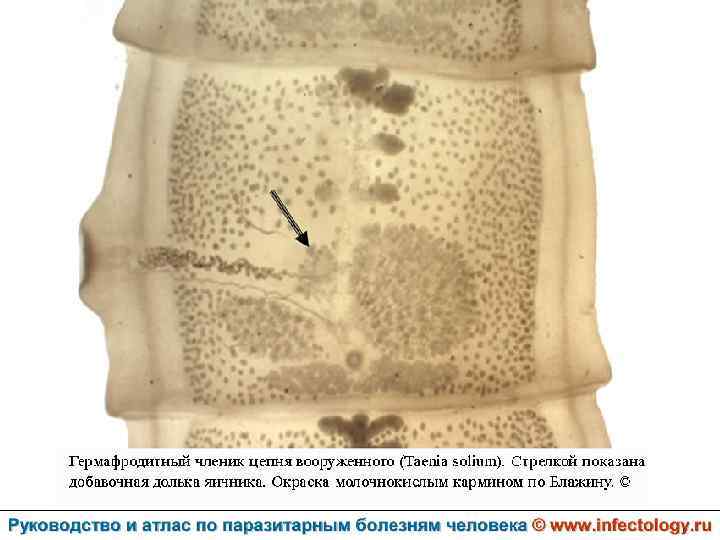

Тениоз (шифр по МКБ 10 - B 68. 0) – антропонозный биогельминтоз, одним из основных клинических проявлений которого является нарушение функций желудочно– кишечного тракта.